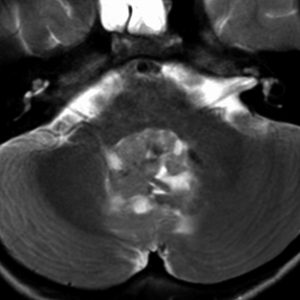

境界が不鮮明で全摘出できない小脳の若年性毛様細胞性星細胞腫

juvenile pilocytic astrocytoma

8歳で無症状でした。正常小脳内に浸潤して境界が不鮮明です。

年齢的にもjuvenile tpyeであり,左のMRI画像のように部分的に増強され,CTでは石灰化も認められました。術前予想としてはローゼンタールファイバーが多くて硬い癒着性腫瘍であることが予想されます。もちろん,仕方がないので亜全摘出を試みます。予想どおり,延髄閂 ovexに癒着した部分が外れませんでした。再燃があれば局所放射線治療を行う予定で経過観察しました。何も症状はなくて元気に育ちました。

11年後の画像です。幸い延髄背側のものは再発せず,自然退縮しました。数年前から,小脳扁桃と中部に小さなガドリニウム増強される再燃病変がありますが,これらはなにもしないでほっておきます。もう患者さんが20歳くらいになるので,このまま大きくならないか,退縮する可能性が高いからです。